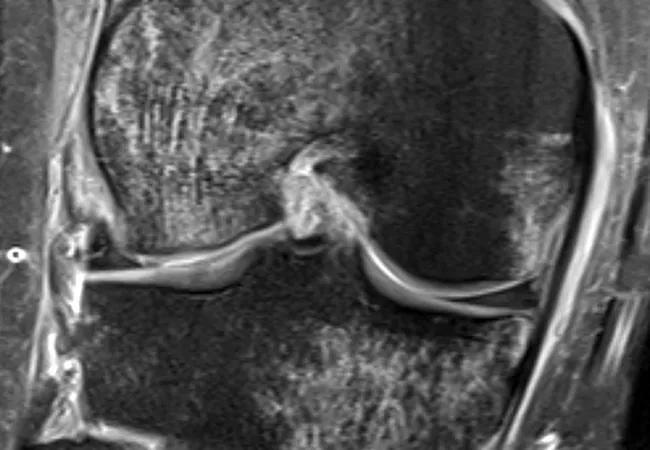

Coronal MRI showing bruising to medial tibial plateau and medial and lateral femoral condyles.

Coronal MRI showing bruising to medial tibial plateau and medial and lateral femoral condyles one month after ACL rupture in a 28-year-old patient.